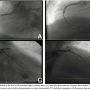

Hg. ECG demonstrated initially normal sinus rhythm, ST-segment elevation in leads II, III, aVF, and in leads V1-4 (Figure 1). The patient received aspirin, 600 mg of clopidogrel, unfractionated heparin, and front loading of glycoprotein IIb/IIIa inhibitor (tirofiban) followed by infusion. He was referred for urgent cardiac catheterization. Upon arrival to the cardiac catheterization laboratory, an intra-aortic balloon pump was placed for hemodynamic support. Coronary angiography showed occlusion of the proximal right coronary artery (RCA) and the proximal left anterior descending (LAD) coronary artery (Figure 2). The procedure was complicated by more than 20 episodes of ventricular fibrillation requiring resuscitation. Percutaneous balloon angioplasty and placement of 2 stents resulted in TIMI III flow in both the LAD and RCA. Echocardiography immediately after PCI showed a left ventricular ejection fraction of 46% with hypokinetic anterior wall. He was maintained on dual antiplatelet therapy with aspirin and clopidogrel.